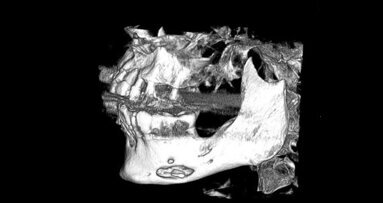

Zdjęcie cefalometryczne potwierdziło hipotezę, iż budowa twarzoczaszki jest nieprawidłowa i cechuje ją nadmierna długość trzonu żuchwy, typowa dla progenii. Stwierdzono całkowity zanik części zębodołowej żuchwy i równocześnie zaawansowany zanik trzonu żuchwy na wysokość. Otwory bródkowe zlokalizowane były ok. 2-3 mm poniżej górnego brzegu trzonu żuchwy. Oceniono również stan tkanek miękkich i stwierdzono, iż na górnym brzegu trzonu żuchwy występuje bardzo wąska (szerokości ok. 1-2 mm) strefa rogowaciejącej dziąsła, do którego bezpośrednio od strony przedsionkowej przylegają przyczepy mięśni. Na podstawie TK ustalono szczegółową budowę kości.

Na podstawie badania TK stwierdzono zachowanie stosunkowo dużej ilości tkanki kostnej, zarówno w wymiarze pionowy, jak i poziomym. Struktura kości charakteryzowała się dużą zawartością warstwy gąbczastej (słabo wysyconej w TK), a także bardzo ograniczoną warstwą kortykalną kości. W związku z tym zaplanowano wszczepienie większej liczby implantów niż w standardowym postępowaniu. Wykonany został szablon chirurgiczny z poziomu tkanek miękkich na podstawie badania TK. Wszczepienie implantów rozłożone zostało na 2 etapy, spowodowane ekstrakcją zębów 16 i 13.